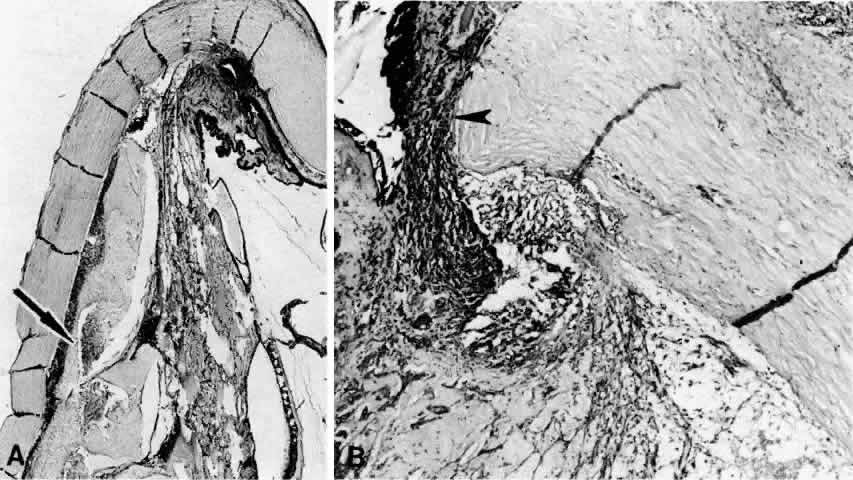

Fig. 8. This choroidal and ciliary body detachment, which occurred after intracapsular cataract extraction, was mistaken for a malignant melanoma.39 A. Iris incarceration in the wound (arrow) and extensive ciliary body effusion consisting of a dense, proteinaceous material (asterisk) (H & E, × 115). B. Effusion of the choroid near the ora serrata by a moderately dense, proteinaceous material without inflammatory cells. Note folds of choroid (arrowheads) (H & E, × 115).

Fig. 9. A. This serosanguineous ciliochoroidal effusion (arrow), which occurred after iridectomy for an iris melanoma in a 68-year-old man, was mistaken for a choroidal melanoma (H & E, × 25). B. Site of the limbal wound (arrowhead) with incarceration of the iris base and residual melanoma in the iris, anterior aspect of the ciliary body, and trabecular meshwork (H & E, × 60).

Fig. 10. A. This extensive ciliochoroidal effusion (asterisk), which occurred 4 years after iridencleisis in a 70-year-old man,39 was mistaken for a malignant melanoma. The iris (arrow) is incarcerated in the limbal wound, and a flat, edematous infiltration bleb (arrowheads) is present (H & E, × 25). B. Area of the ora serrata shows a ciliochoroidal effusion with proteinaceous material separating the tangentially oriented collagen fibers (arrowheads) that connect the choroid and ciliary body to the sclera (H & E, × 115).